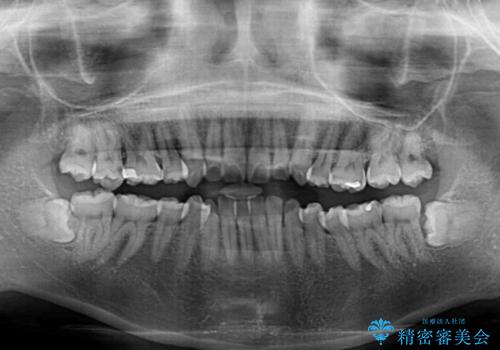

- 前歯のデコボコを治したいとのことで来院された患者様です。

上下顎ともに歯列全体の後方移動とIPR(歯と歯の間を削る)によってデコボコが解消するように設計し、インビザラインにより治療を行うこととしました。